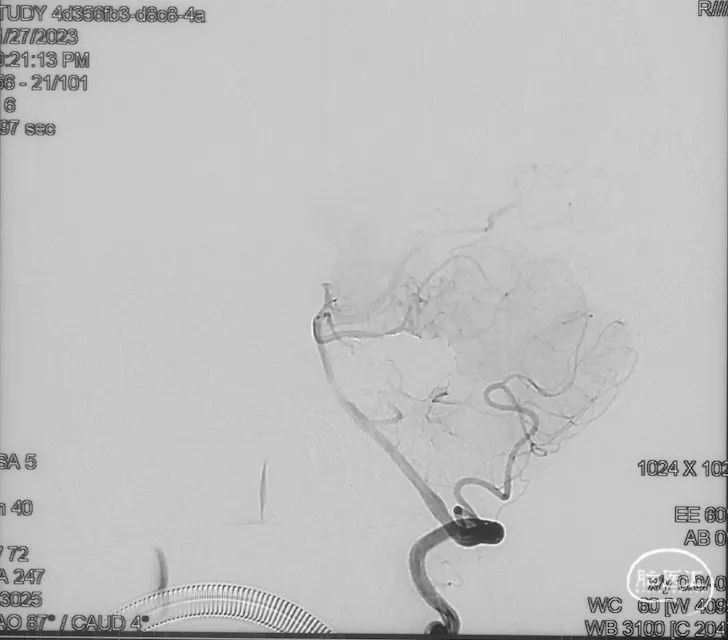

治疗结果

双侧颈外、颈内动脉正侧位造影瘘口均不显影

双侧椎动脉造影未见瘘口显影,可见广泛皮层静脉瘀滞

Onyx胶铸型显示瘘口形态。